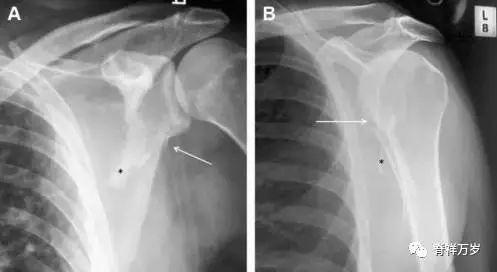

图 3 肩胛骨骨折正侧位片:由于骨块的叠加,(A)前后位片示「V」形高密度影(*),肩胛颈下方可见骨皮质碎片(箭头);(B)侧位片示骨皮质中断,骨折段移位,但由于肱骨的重叠遮挡,决断往往比较困难。